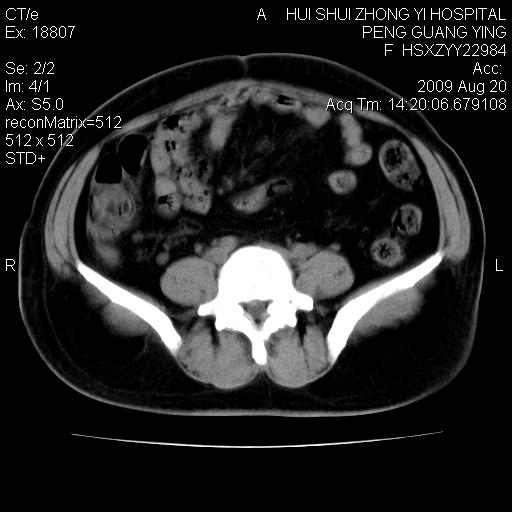

标题: CT21707:女,42岁,因发现下腹部包块2月。 [打印本页]

标题: CT21707:女,42岁,因发现下腹部包块2月。

增强看看,倾向于子宫肌瘤并囊变或腺肌征,宫腔少量积液。

病灶来源——子宫?附件?

从平扫角度看本人还是倾向于子宫肌瘤诊断,宫腔少量积液。

目前的影像表现显示肿块位于腹腔及盆腔,但具体定位,分清来源较困难,是否来源于卵巢、子宫无法定论,子宫直肠及子宫膀胱周围脂肪间隙尚较清晰,如果患者有过腹腔好或者盆腔手术史,也可以形成不典型的血中,最好手术后定为定性,我期待结果。

软组织密度,与子宫一致。双侧卵巢形态、密度好,不支持来源于卵巢。